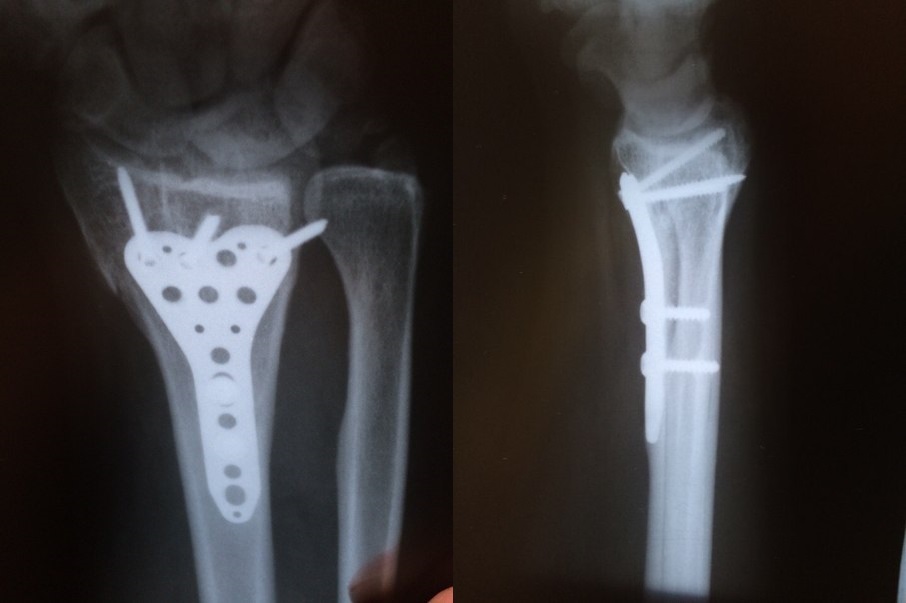

И мне недавно поставили. Точно такую же штуку как на рентгене у автора.. И нога так же левая, и даже средний болт так же торчит с другой стороны=)

Вот только на второй кости еще два шурупа. Очень хочется уже поскорее начать нормально ходить. Ну что ж, всем "киборгам" скорейшего выздоровления=)

У меня тоже стоит. Но ничего про снятие не говорили. Мешает зараза. Стопа не до конца сгибается.

Насколько я поняла, ее ставят временно, на год.. Чтобы кости срослись правильно и ничего не мешало в будущем подвижности стопы.. Плюс, дополнительная жесткость при нагрузке.. А потом, пластина уже не нужна.. У меня подвижность стопы полностью восстановлена, спасибо врачам и физиотерапевтам

Стальная.. Ее ставили на год, изначально планируя в итоге снять.. Дядя-доктор объяснил, что в мне не стоит оставлять в организме металл.. Да и потом, она немного выпирала.. Я ее пальцами могла прощупать.. Брррр